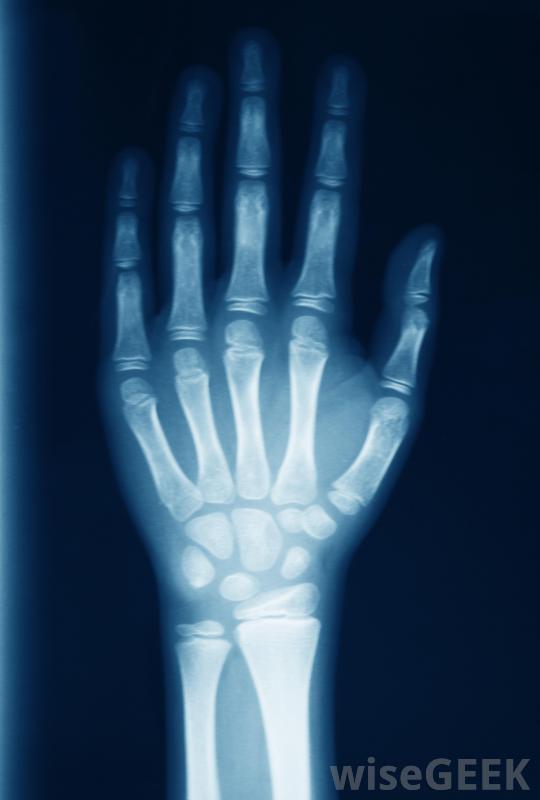

可以使用x光檢查骨折的手指。